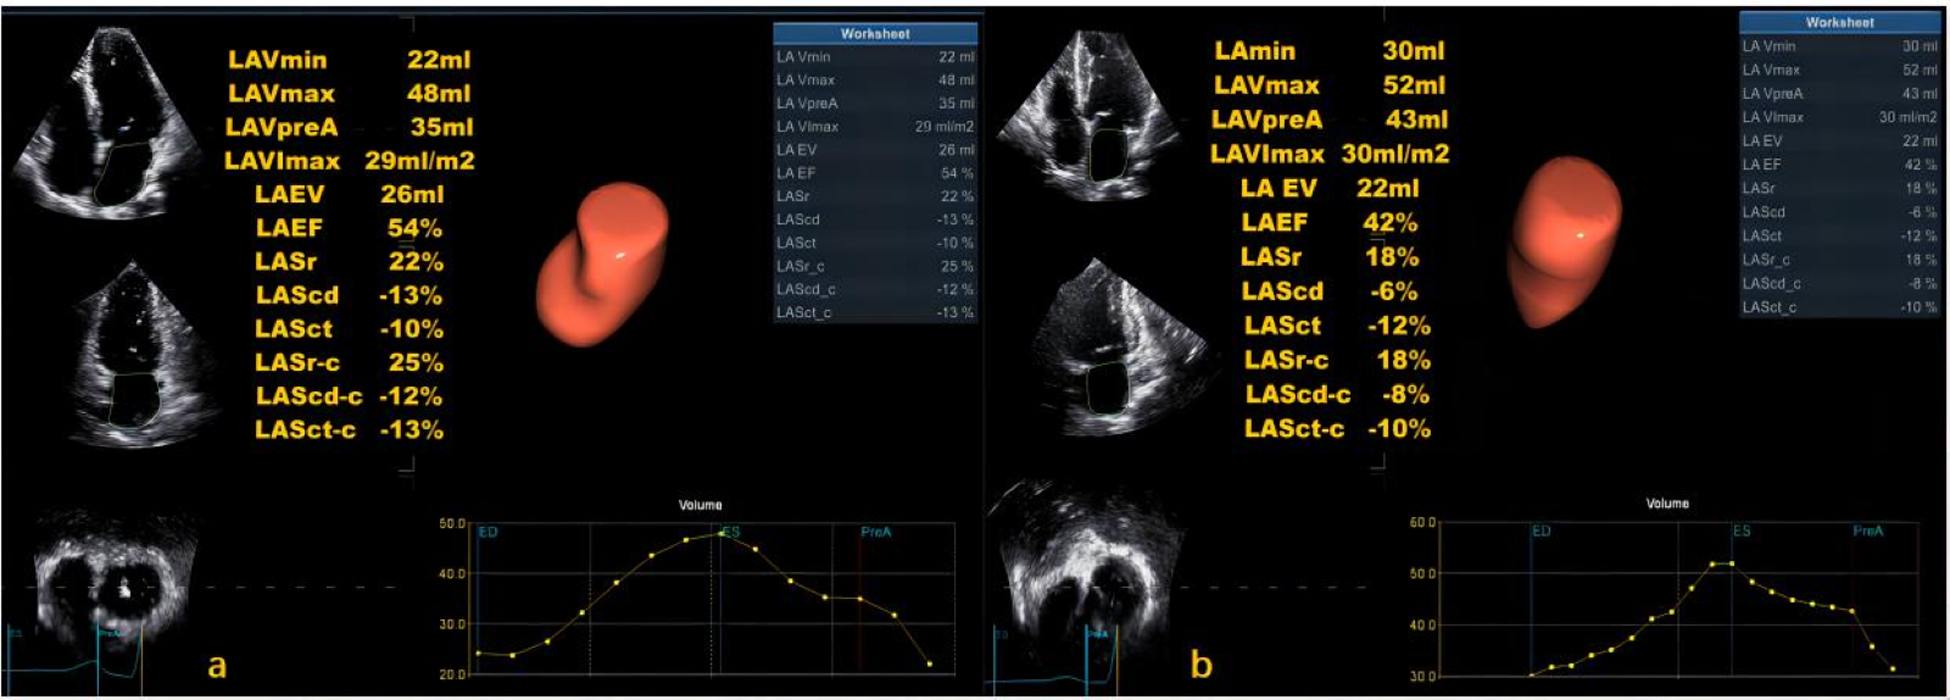

The LASI, derived from left atrial strain, showed a consistent upward trend, being significantly higher in the HT-HFpEF group (P < 0.05),specifically, the ratio of E/e' to LASr was 0.58 (0.52, 0.66) in the HT-HFpEF group vs. 0.46 (0.33, 0.59) in the HT group, similarly, the ratio of E/e' to LASr-c was 0.5 (0.38, 0.6) vs. 0.36 (0.27, 0.43). These findings emphasize LASI as key index for evaluating impaired atrioventricular compliance in HT-HFpEF patients, underscoring its critical role in detecting atrioventricular dysfunction in this population (Table 3). Conversely, no significant differences were observed in LAScd and LAScd-c between the HT and HT-HFpEF groups, indicating that conduction function remains preserved (P > 0.05). Figure 2 presents an example of different time-phase 3D LA volume and strain parameters for HT-HFpEF and control patient. Figure 3 depicts the points utilized for determining circumferential strain lines.

Figure 2

Three-dimensional (3D) left atrial volume and strain analysis for a control patient (a) and HT-HFpEF patient (b).